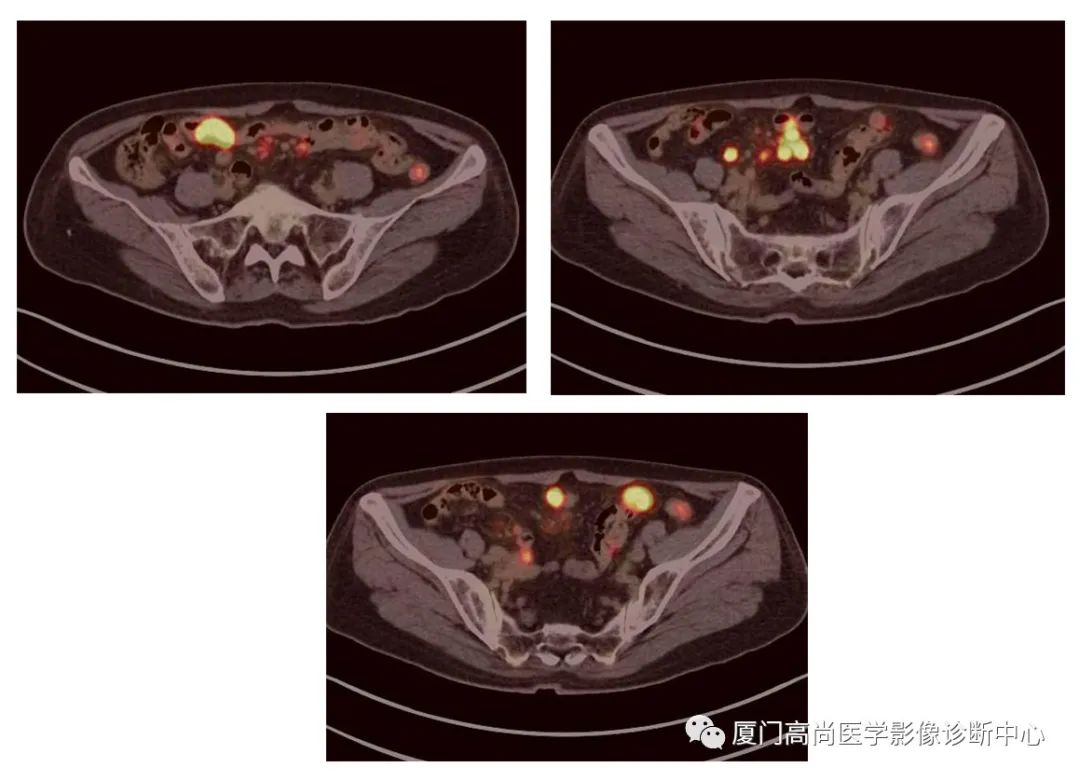

腹腔淋巴結(jié)腫大

PET/CT發(fā)現(xiàn) :左心房、右心房見團(tuán)塊狀FDG攝取增高;雙側(cè)腎上腺增大,F(xiàn)DG攝取增高;膽囊和胃壁結(jié)節(jié)樣FDG攝取增高;小腸多節(jié)段腸壁增厚,F(xiàn)DG攝取增高;腹膜后、腹腔及盆腔多發(fā)淋巴結(jié)腫大,F(xiàn)DG攝取增高;上述考慮為淋巴瘤

經(jīng)腎上腺穿刺活檢 :病理證實(shí)為彌漫大B細(xì)胞淋巴瘤